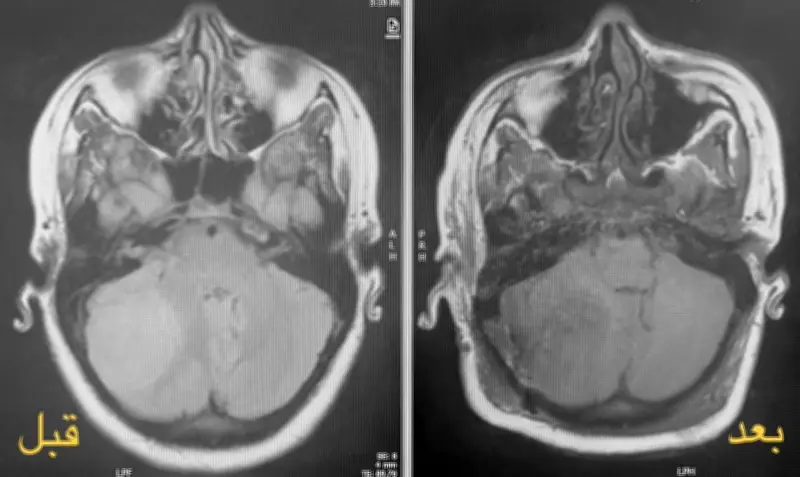

تطلبت الحالة الطبية تدخلاً جراحياً عاجلاً بسبب تشخيص ورم دماغي خطير لدى المريضة، التي كانت في مرحلة متقدمة من الحمل. شكلت العملية تحدياً كبيراً للفريق الطبي، حيث كان من الضروري إزالة الورم بالكامل مع ضمان عدم تعريض حياة الجنين لأي مخاطر.

أعلنت مدينة الملك سلمان الطبية أن العملية جرت بنجاح تام، حيث تم استئصال الورم الدماغي بالكامل دون أي مضاعفات. كما تم الحفاظ على سلامة الجنين طوال فترة التدخل الجراحي، مما يعكس الكفاءة العالية للفريق الطبي والبنية التحتية المتطورة للمستشفى.